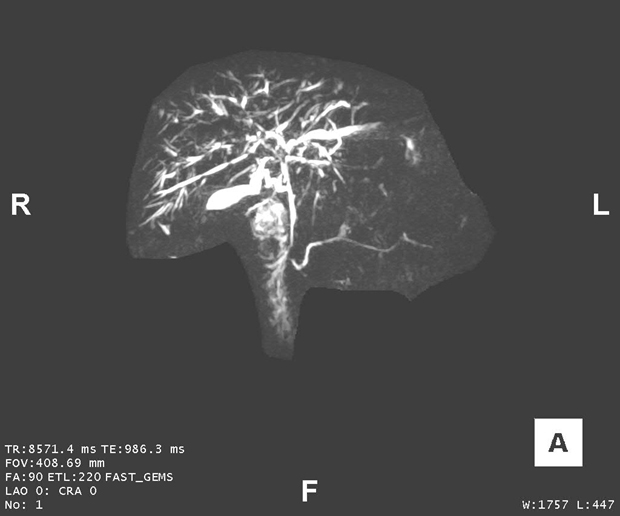

Here is a key image of the MRCP (figure 1)

Image from the library of Mayo Clinic

Figure 1. MRCP image demonstrating PSC strictures in the bile duct. Note strictures of the intrahepatic ducts and the perihilar extrahepatic duct, with prestenotic dilatation, particularly of the left hepatic duct.

The classic appearance on imaging (i.e., cholangiography) of the bile ducts with PSC is multifocal narrowing with intervening segments of prestenotic ductal dilatation. This appearance is often described as a beaded pattern. Focal strictures of the extrahepatic bile ducts or larger hepatic ducts are often referred to as “dominant strictures,” and strictures that cause obstructive cholestasis or bacterial cholangitis are termed “relevant strictures.” A less common variant of PSC is known as “small-duct PSC,” which is characterized by typical cholestatic and biochemical features of PSC, but cholangiogram findings demonstrate normal bile ducts.

The diagnosis of PSC is typically confirmed through cholangiography, revealing characteristic bile duct strictures and dilations. Noninvasive imaging of the biliary system with MRCP — an MRI protocol to optimally visualize the biliary tree — is the test of choice. An MRCP has high sensitivity for visualizing bile duct abnormalities.